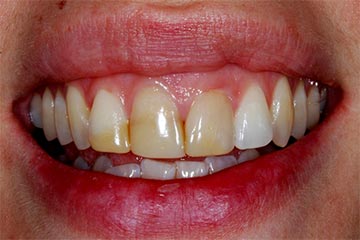

Faccette estetiche in ceramica